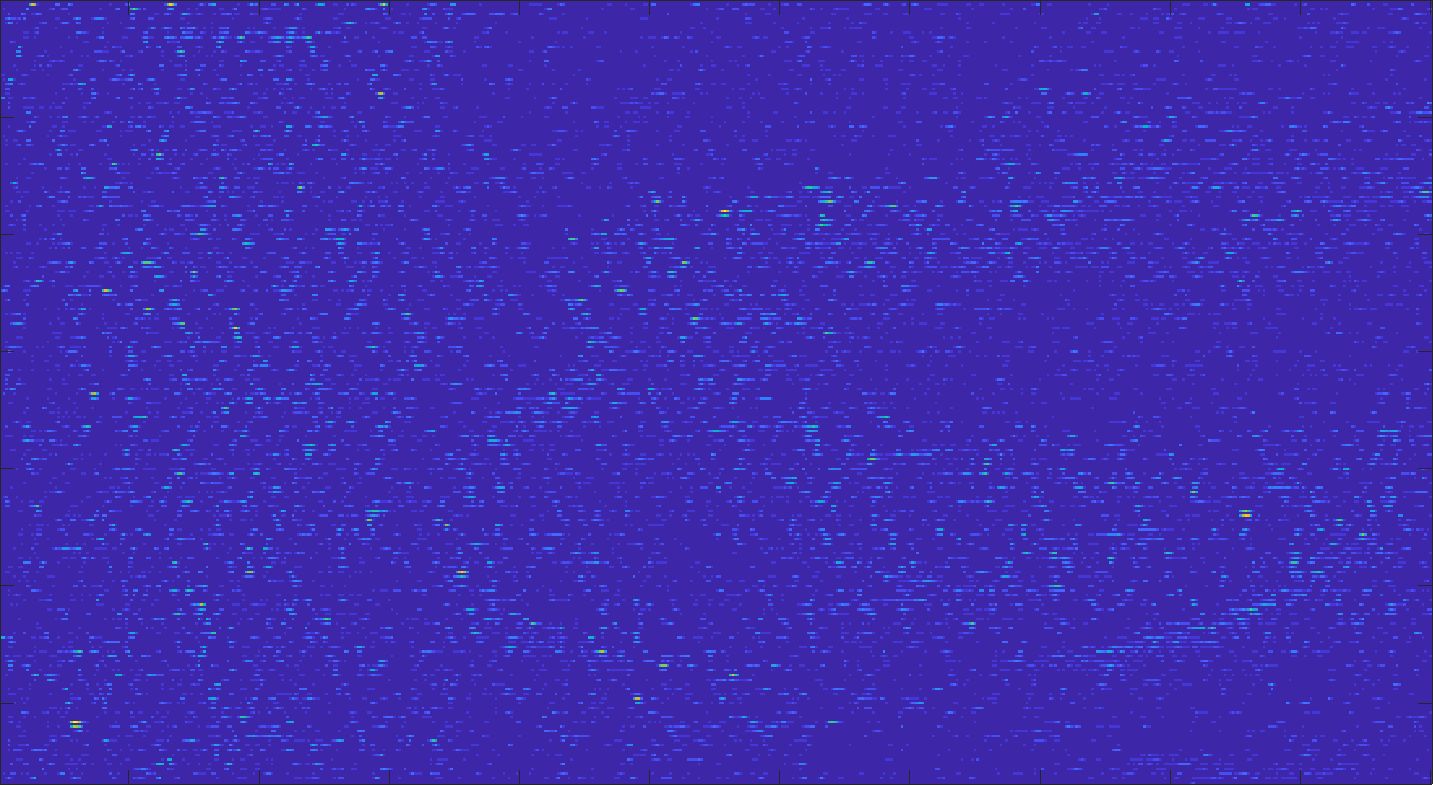

Our framework visually improves the results, in terms of blurring and artefacts. This result is more evident in the magnification of the ear of the foetus (Fig. 3), the mitral valve (Fig. 4), and the mass edges (Fig. 5). Fig. 6 shows the error image of the three anatomical districts with both 2X and 4X up-sampling factors, with the maximum error in the scale . The error is more evident in the contours of the anatomical structures; moreover, the abdominal district shows a smaller error than the cardiac and obstetric ones. We underline that the view for each image is scaled to its maximum, to improve the visualisation of the error.

The analysis of the absolute value of the difference between the input and the prediction of the network (Fig. 9) shows that the alteration of our prediction to the pixel values ranges from 0 to a maximum absolute value of 20, mainly located on the edges of the anatomical structures; furthermore, the black uniform areas are less affected by the prediction. In terms of the distance between the input and the prediction, we do not observe a significant difference among anatomical districts and between 2X and 4X up-sampling.